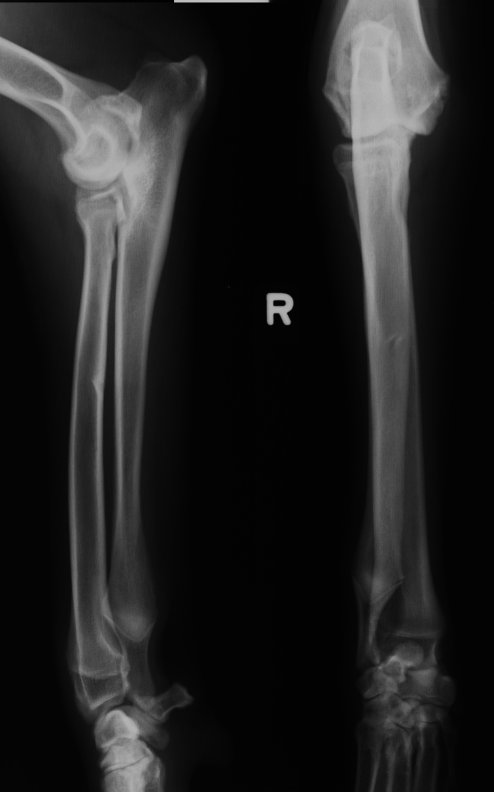

signalment for fungal osteomyelitis

systemically ill

young to middle age

large working/sporting breeds

polyostotic

lysis and production

metaphysis

AGG lesion

fungal osteomyelitis